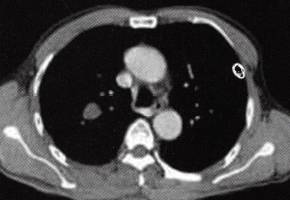

图1肺错构瘤

D

D.增强扫描结节灶无明显强化

(1)病灶直径多<2.5 cm,边缘光滑,可浅分叶。 (2)病灶密度不均匀,可见短条状钙化,典型征象为“爆米花样”钙化,部分见脂肪密度影。 (3)增强扫描病灶无明显强化。 2)中央型: (1)支气管腔内结节,边缘光整,可见钙化。 (2)附着处支气管壁无侵蚀增厚。 (3)远端支气管阻塞性肺炎和/或肺不张改变。 4.MRI表现: 周围型结节显示信号不均勻,脂肪成分显示优于CT,可确诊。影像学检查显示肺周围境界光整的孤立性结节,见有“爆米花样”钙化或脂肪组织即可确诊。 【分析思路】 诊断依据: 1.患者为男性,63岁。无症状,偶然发现。 2.右肺孤立性结节,边缘光滑,无分叶,结节内多个点条状钙化,有脂肪样密度影,增强扫描病灶无明显强化。 3.无肺门、纵隔淋巴结增大及胸腔积液。 鉴别诊断: 1.周围型肺癌:①多为大于3 cm的肿块。②结节型多边缘毛糙,见“短毛刺征”“分叶征”。③病灶密度多不均勻,可见“空泡征”。④偶见点状钙化。增强多为明显强化。⑤本例结节灶未见肺癌常见征象,也未见肺门及纵隔淋巴结肿大、胸腔积液,所以不符合肺癌影像学表现。 2.结核球:①多位于两上肺。②结节灶单发多见,边缘锐利,无分叶,多有钙化等良性征象。③结核结节周围常见“卫星灶”,结节中央干酪样坏死密度低,钙化为点簇、层环样表现,增强如有强化则多呈环状强化。④本例结节内钙化形态呈短条样且见脂肪密度影,病灶周围肺野清晰,所以不支持结核球诊断。 3.肺内其他良性肿瘤:①与此例类似征象如:结节灶光整,无分叶。②无此例结节灶内所见钙化形态、数量和脂肪样密度征象,所以不考虑其他罕见良性肿瘤诊断。 4.肺动静脉瘘:①与此例类似征象如:孤立结节、边界光整、无分叶。②动静脉瘘增强扫描可见特征性的病灶明显强化及引流血管影征象,所以不符。